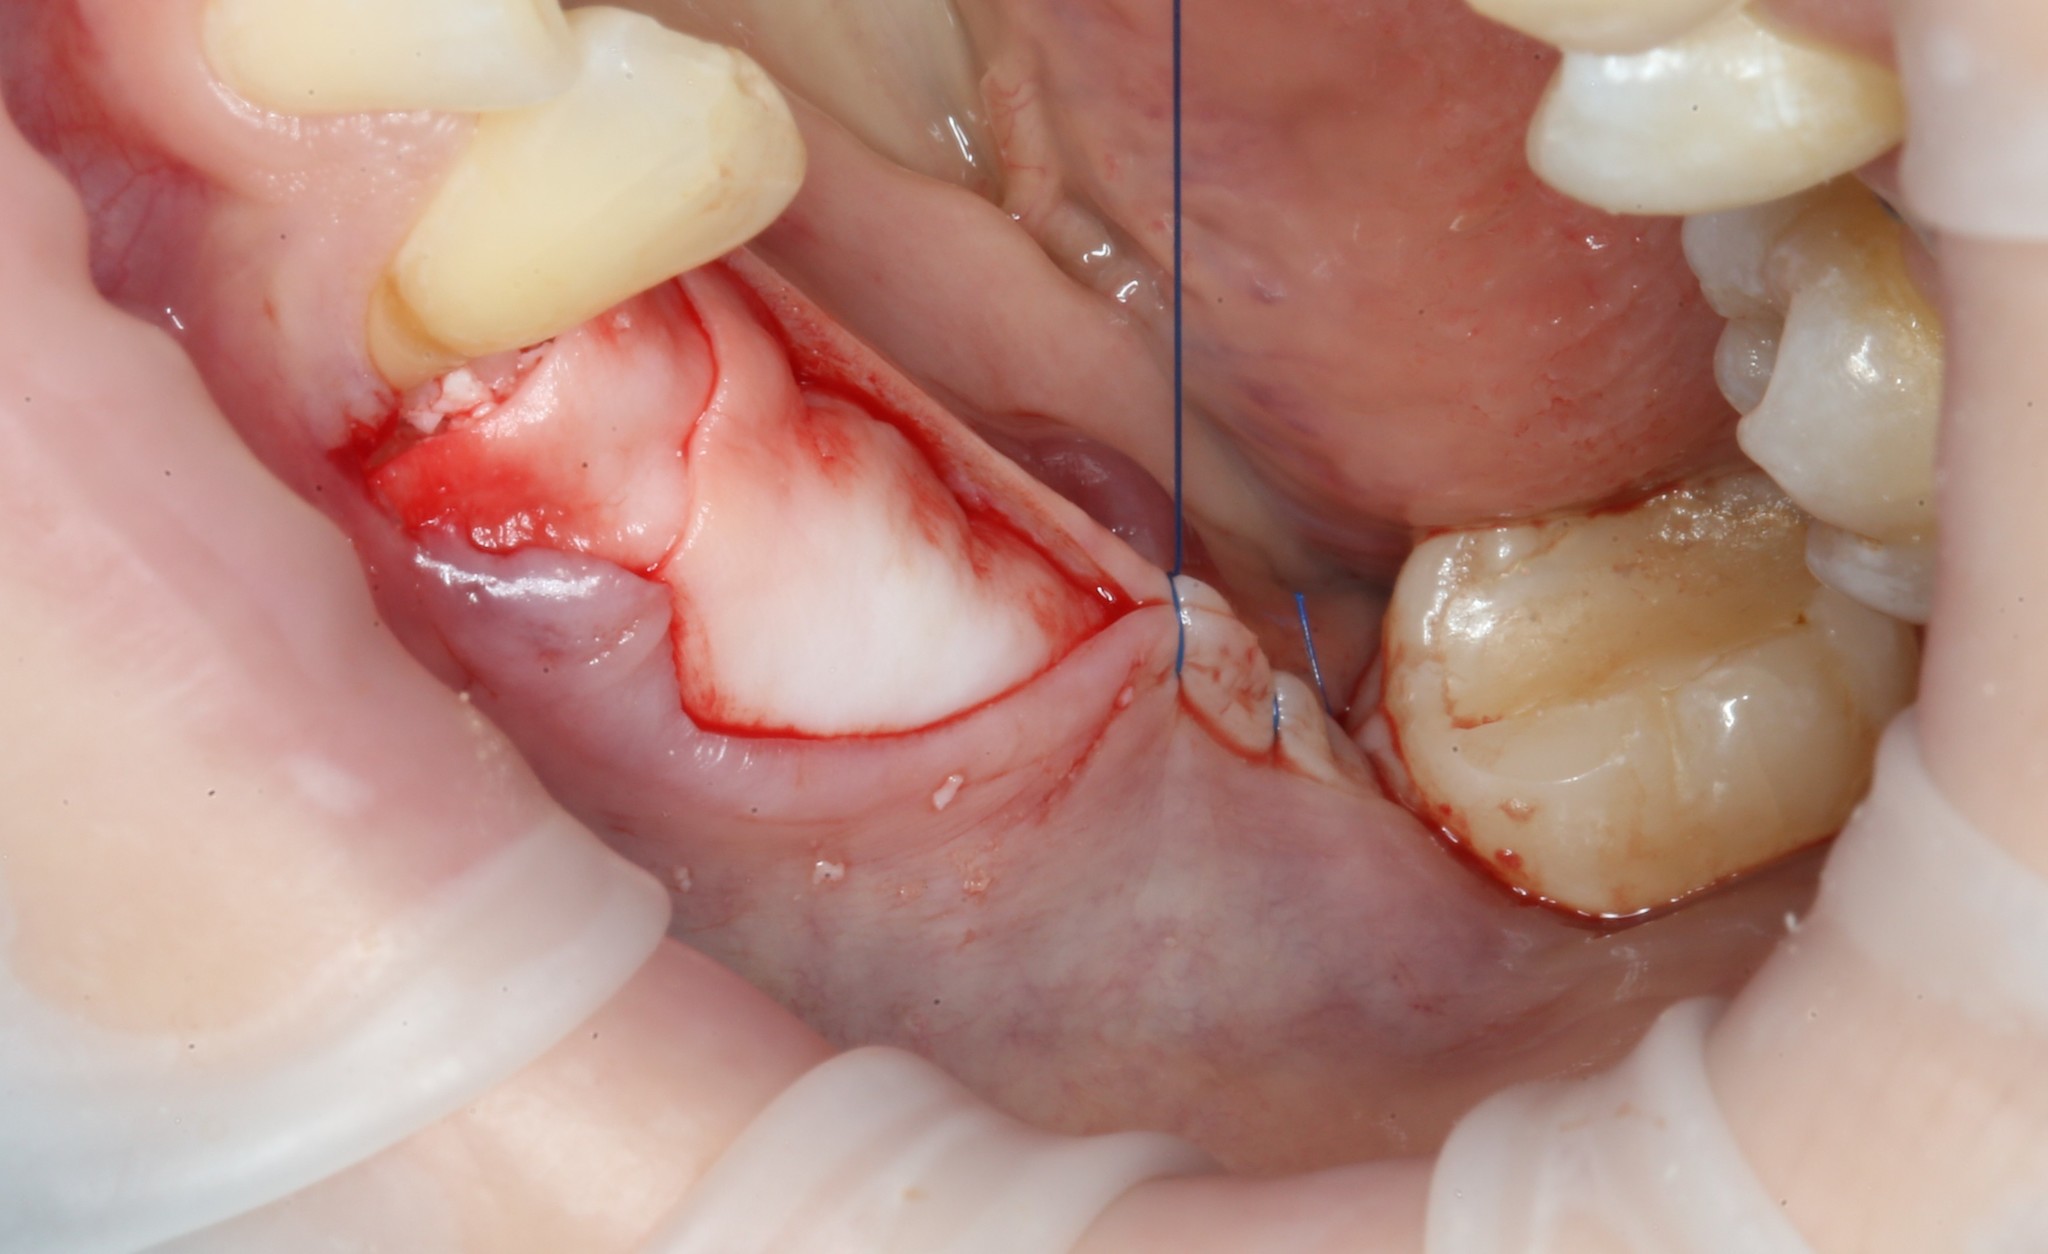

Итак, 5 месяцев позади:

Всё тот же разрез и скелетирование кости: